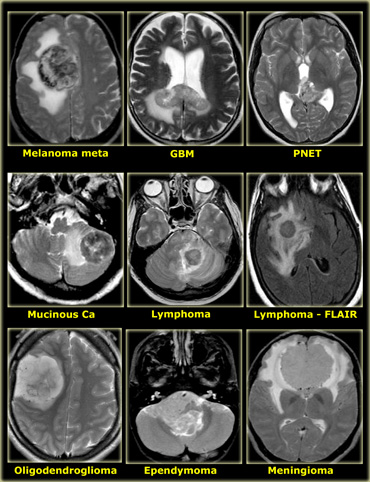

Low on T2

Most tumors will be bright on T2WI due to a high water content.

When tumors have a low water content they are very dense and hypercellular and the cells have a high nuclear-cytoplasmasmic ratio.

These tumors will be dark on T2WI.

The classic examples are CNS lymphoma and PNET (also hyperdense on CT).

On the left some examples of tumors with a low signal intensity on T2WI.

1. Melanoma metastases have a low SI on T2WI as a result of the melanin.

2. GBM can have a low SI on T2WI because sometimes they have a high nuclear-cytoplasmic ratio. Most GBM's, however, are hyperintense on T2WI.

3. PNET typically has a high nuclear-cytoplasmic ratio. PNET is mostly located in the region of the 4th ventricle, but another, less common, location is in the region of the pineal gland.

4. Mucinous metastases can have a low SI on T2WI because they often contain calcifications..

5. Meningiomas are mostly of intermediate signal.

They can have a high SI on T2WI if they contain a lot of water.

They can have a low SI on T2WI if they are very dense and hypercellular or when they contain calcifications.